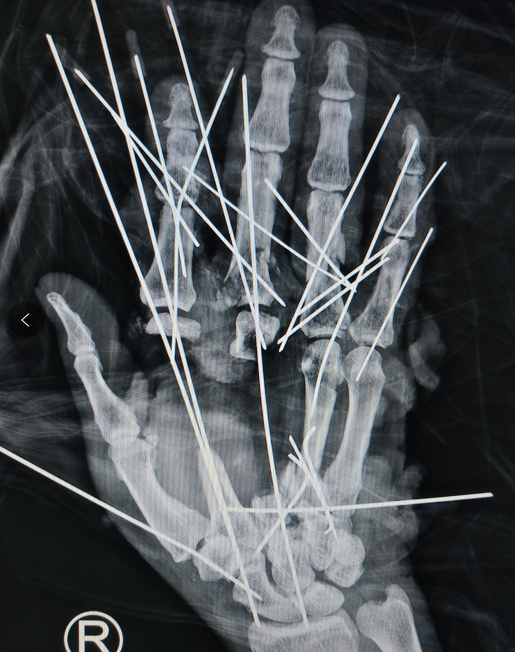

经检查发现,刘师傅右手多段离断,掌指骨碎成了十多块,肌腱、血管、神经多段离断伴缺损。

术中李医生手术团队为刘师傅把一根一根钛克氏针扎在他的手上进行骨折关节复位,一根,两根......直到21根,触目惊心,然后依次吻接受伤的血管、神经和肌腱,最终经过了六个多小时,手术顺利完成,刘师傅安返病房。